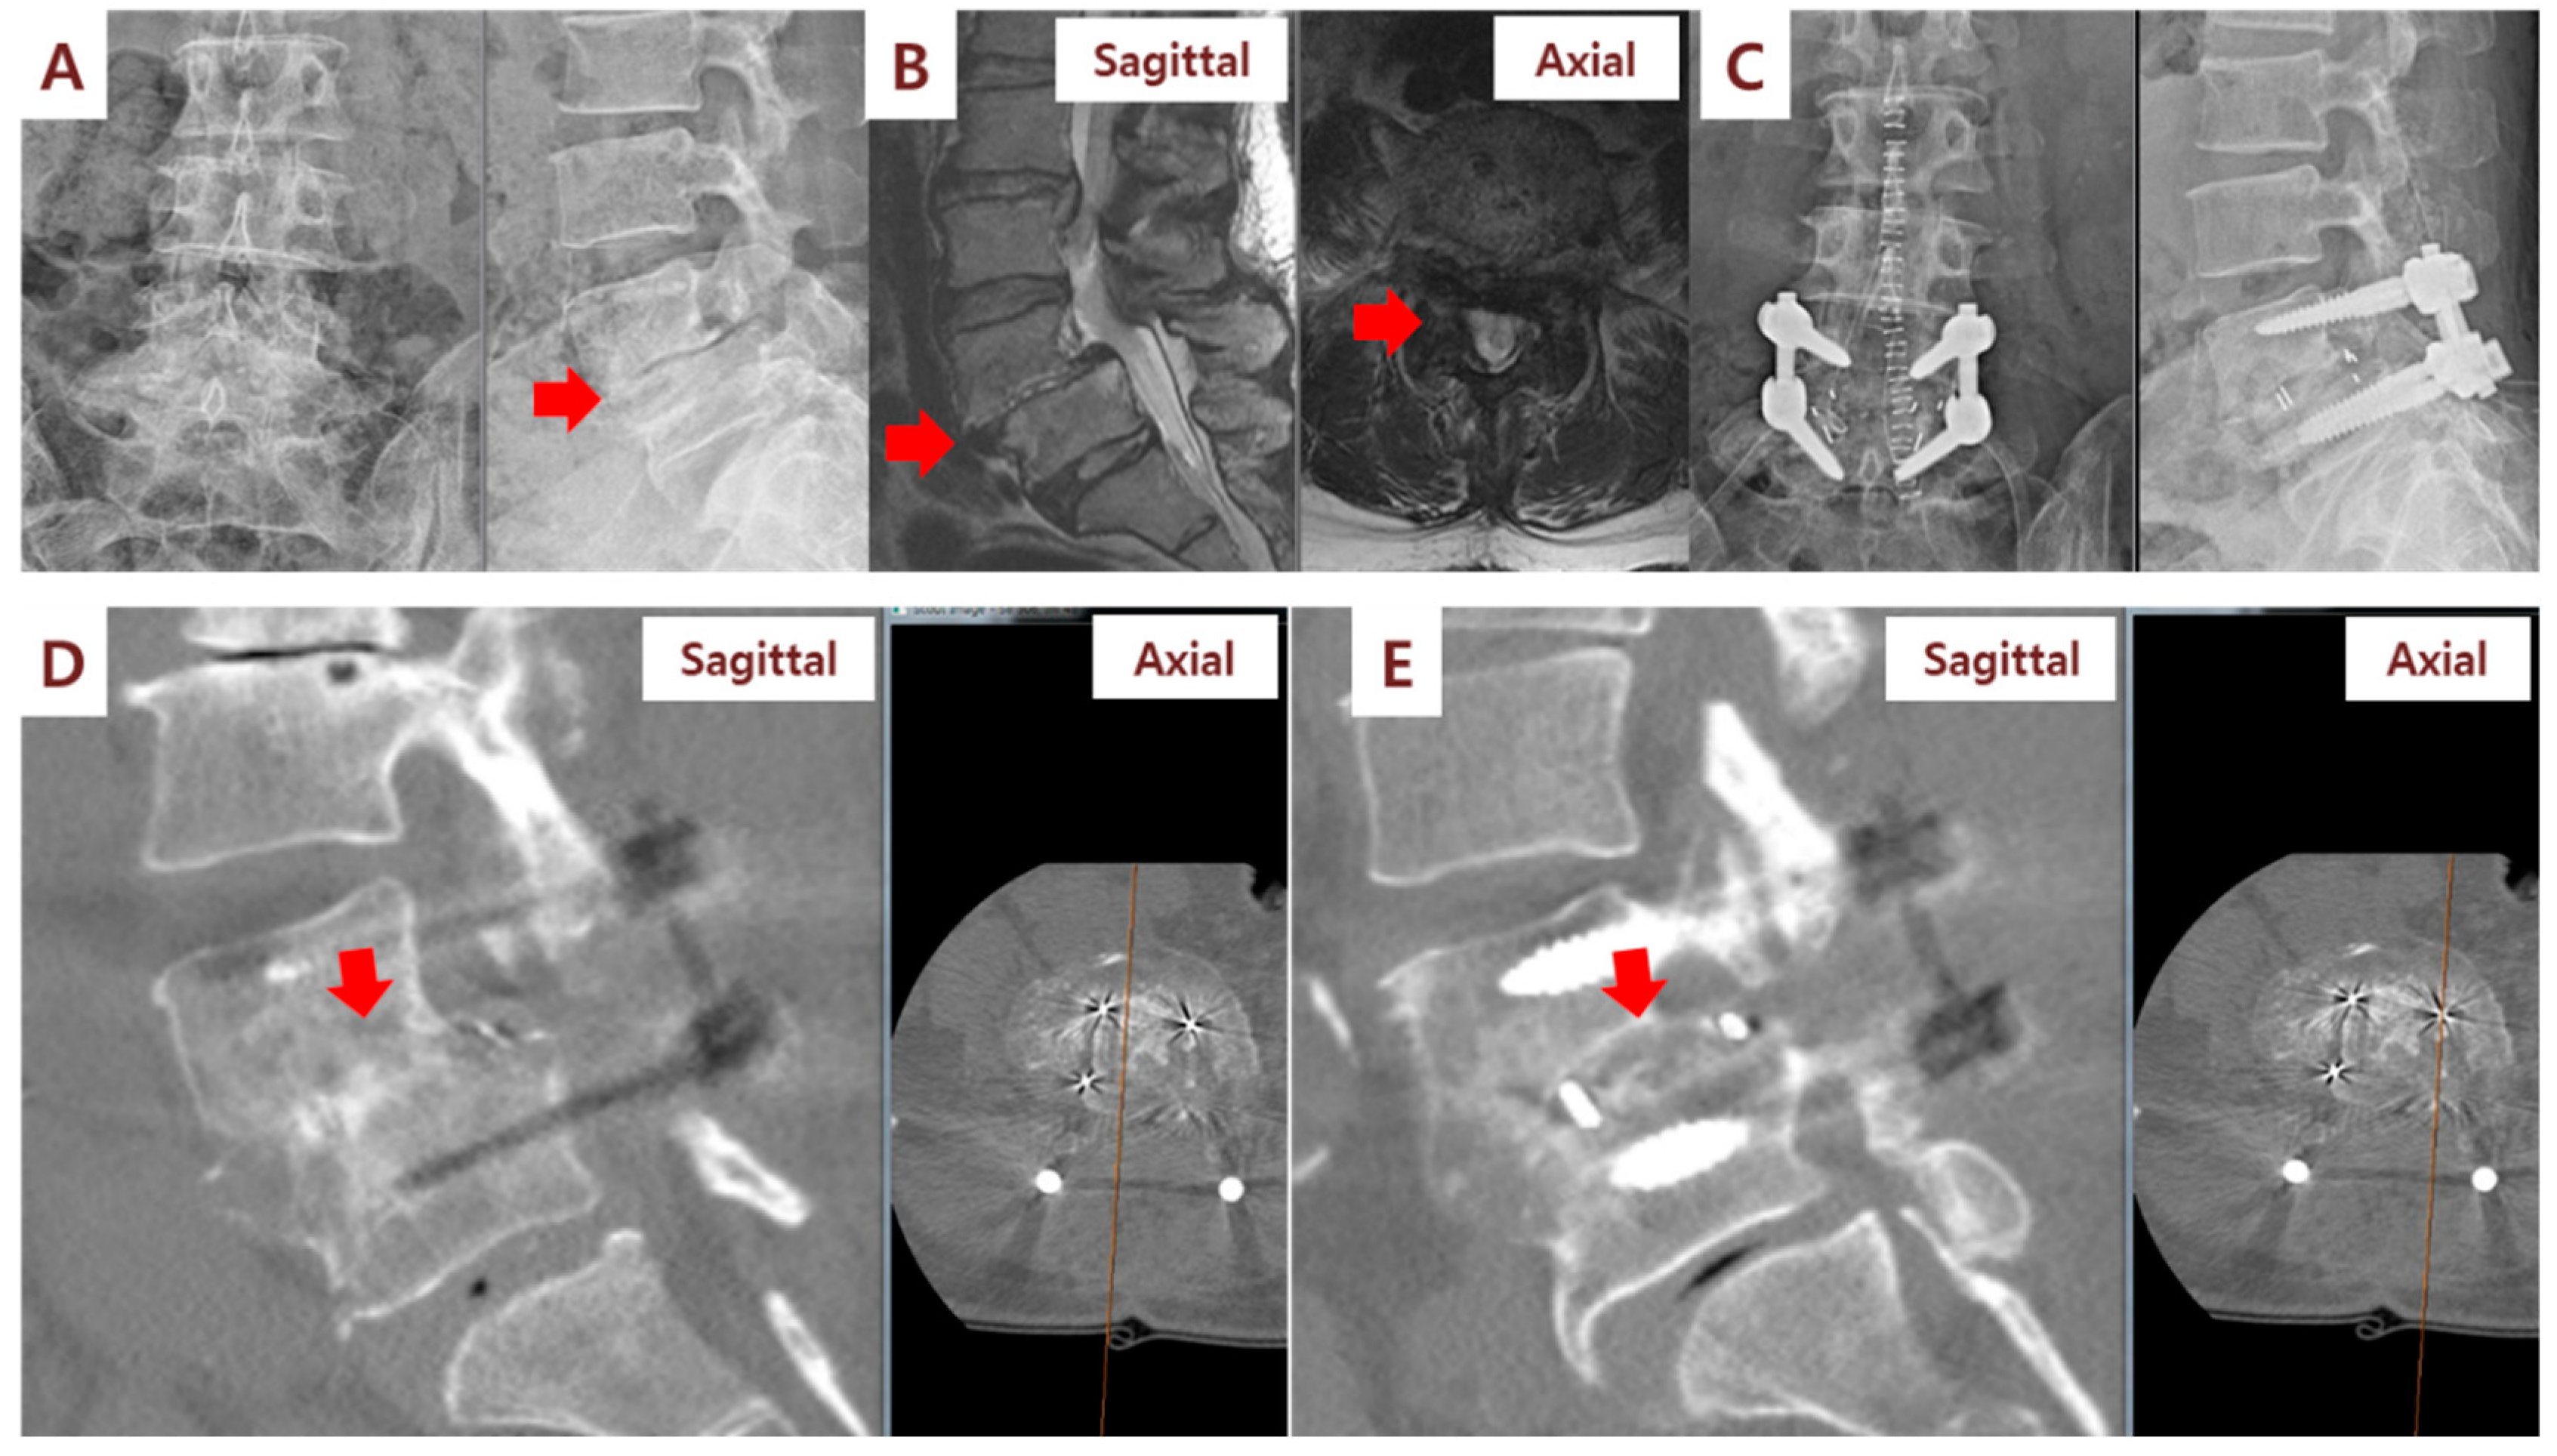

Figure 3.

Illustration case (Patient No. 1): A 60-year-old woman received posterior lumbar interbody fusion and pedicle screw fixation. Preoperative lumbar spine standing anteroposterior and lateral view (A) and magnetic resonance imaging (MRI) (B) demonstrating L4/L5 severe spinal stenosis with degenerative spondylolisthesis. (C) Postoperative lumbar spine standing anteroposterior and lateral view. (D) Computerized tomography (CT) sagittal view performed at 6 months after surgery showed fusion status (red arrow) of cages filled with SVF and β-TCP mixture on the right side of the patient. (E) CT sagittal view showed no fusion status (red arrow) of cages filled with β-TCP alone on the left side.